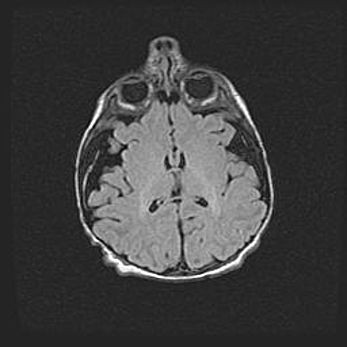

Лейкомаляция с кистозно-глиозной дегенерацией головного мозга.

Возраст: 2 месяца 25 дней

Вес: 6400 г

Окружность головы: 40 см

Срок гестации: 41 неделя

Лейкомаляцию относят к ишемически-гипоксическим повреждениям головного мозга, диагностируемым у новорожденных. При лейкомаляции в головном мозге обнаруживают очаги некроза, возникшие после тяжелой гипоксии и нарушения кровотока. В процессе морфогенеза очаги проходят три стадии: 1) развития некроза, 2) резорбции и 3) формирования глиозного рубца или кисты. Перивентрикулярная лейкомаляция (ПЛ) встречается примерно в 12% случаев среди новорожденных, обычно – у недоношенных детей, причем, частота ее зависит от массы, с которой младенец появился на свет. Наибольшее число малышей страдает лейкомаляцией, если масса при рождении 1500-2500 г.